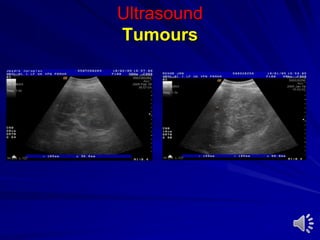

Ultrasound

Tumours